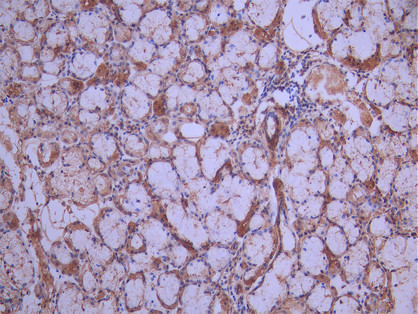

• IHC image of CSB-RA621777MA1HU diluted at 1:50 and staining in paraffin-embedded human salivary gland tissue performed on a Leica BondTM system. After dewaxing and hydration, antigen retrieval was mediated by high pressure in a citrate buffer (pH 6.0). Section was blocked with 10% normal goat serum 30min at RT. Then primary antibody (1% BSA) was incubated at 4°C overnight. The primary is detected by a Anti-Human lgG, Fcy Fragment Specific labeled by HRP and visualized using 0.05% DAB.

• IHC image of CSB-RA621777MA1HU diluted at 1:50 and staining in paraffin-embedded human cervical cancer performed on a Leica BondTM system. After dewaxing and hydration, antigen retrieval was mediated by high pressure in a citrate buffer (pH 6.0). Section was blocked with 10% normal goat serum 30min at RT. Then primary antibody (1% BSA) was incubated at 4°C overnight. The primary is detected by a Anti-Human lgG, Fcy Fragment Specific labeled by HRP and visualized using 0.05% DAB.